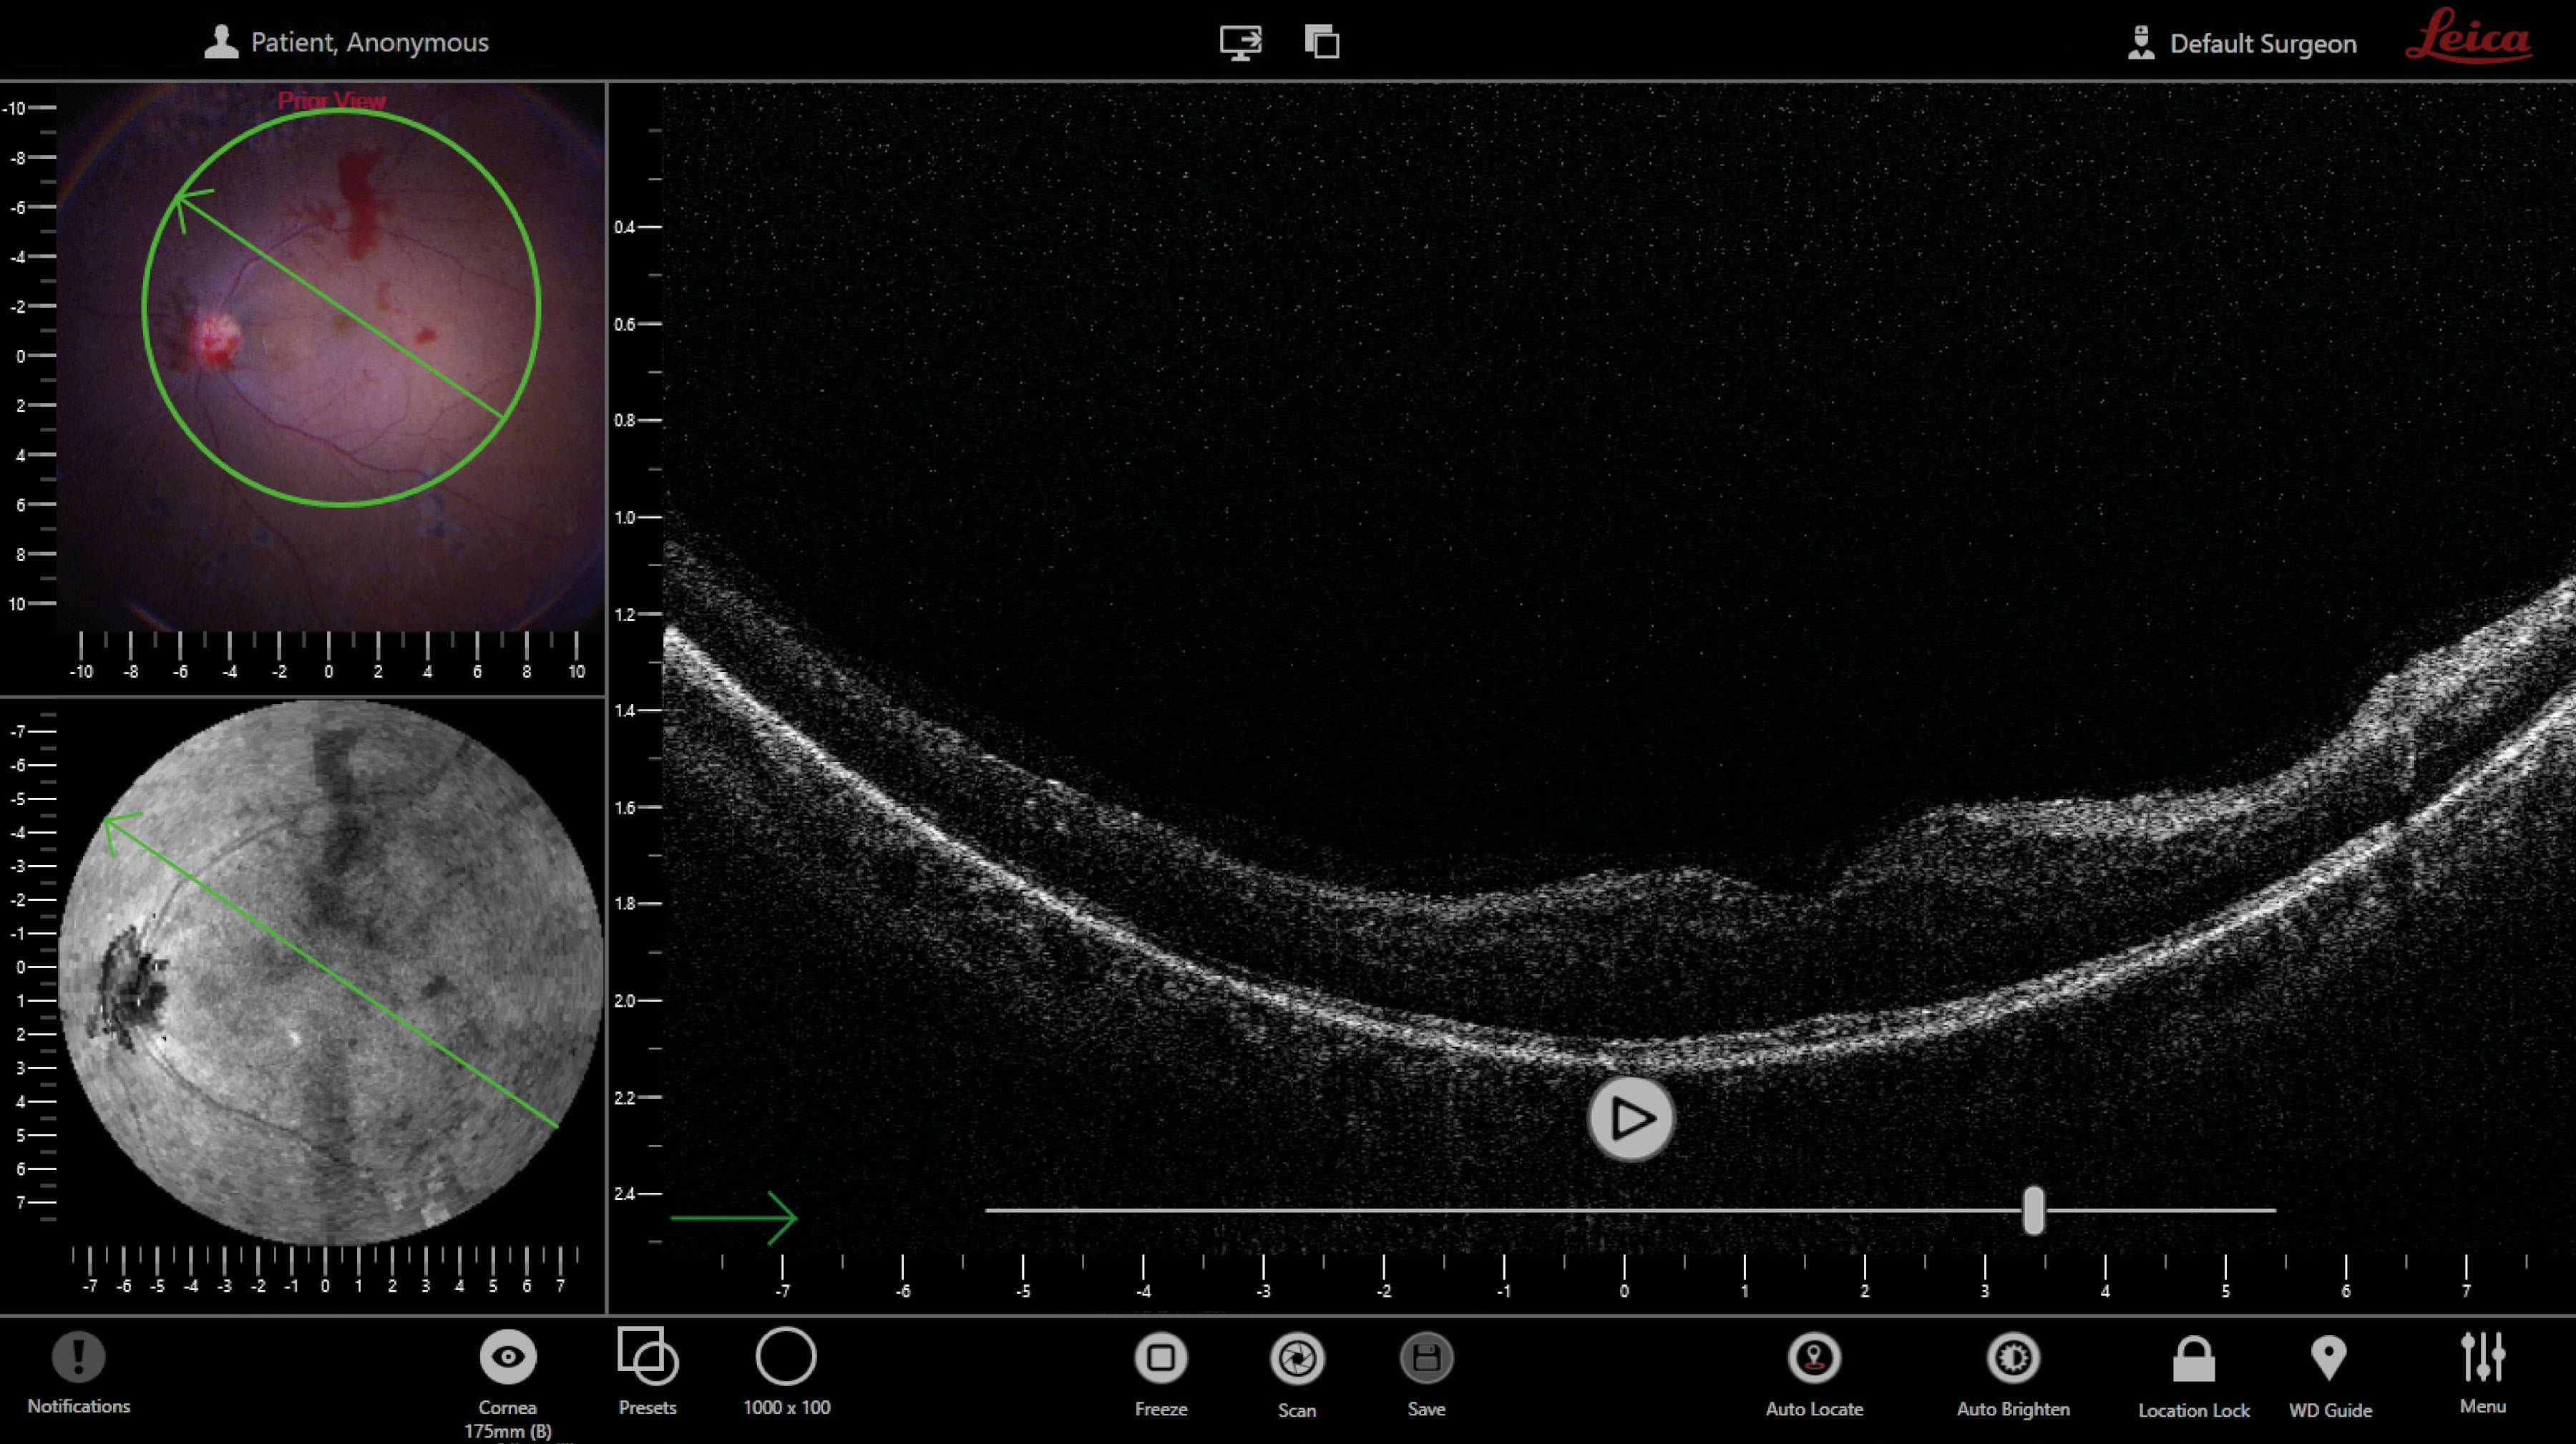

EnFocus术中OCT已整合成为眼科显微镜的一部分,其将最大程度实现外科医生在手术室中的自由度。在显微镜视图的基础上,外科医生可在术中任何时间点轻松补充明亮清晰的术中OCT图像——仅需使用手柄、脚踏开关或触摸屏(图21、22)。 在该成像系统的辅助下,无需单独安排成像技师。EnFocus OCT可在眼科手术期间提供更深入的见解,并可以在术中实时确认组织对手术操作的反应方式。

EnFocus OCT的另一项新功能是允许外科医生在显微镜视野下使用最高反射率进行自动查找组织。例如,在眼前段手术期间,EnFocus将自动聚焦于角膜。当显微镜进一步往下聚焦,将检测到虹膜。如果前房中发生硅油乳化,其反射出的光多于角膜,将替换为焦面。如果使用全景视图系统,新款EnFocus OCT将定位视网膜。如果视网膜脱离或如果存在脉络膜新生血管(CNV),EnFocus将在RPE水平设置焦面。

在Leica Microsystems制造的Proveo 8眼科显微镜中,其脚踏开关可以充分设置为允许外科医生独立变更任何EnFocus术中OCT参数。此外,外科医生可以扫描x轴和y轴上的感兴趣区域,激活自动成像优化功能,并通过直观的用户界面控制OCT的焦距和对比度。使用EnFocus,外科医生还可以轻松采集视频或静态图像。此外,还可以通过脚踏开关轻松调整扫描模式、方向和大小。

在眼科手术中,必须在视觉上对每例手术期间所进行的步骤进行确认。显微镜视图不一定能够充分指导我们进行决策,因其会受到低对比度CNV、出血和萎缩的干扰。如果前房中有非预期混浊并且无法获取放大图像,但同时又要保持相同的图像质量,这种可能性不一定存在。因此,将显微镜的正面彩色视图与可逐层筛查的实时OCT B扫描视图相结合,可提供大量有关表面下组织细节的信息(图23)。